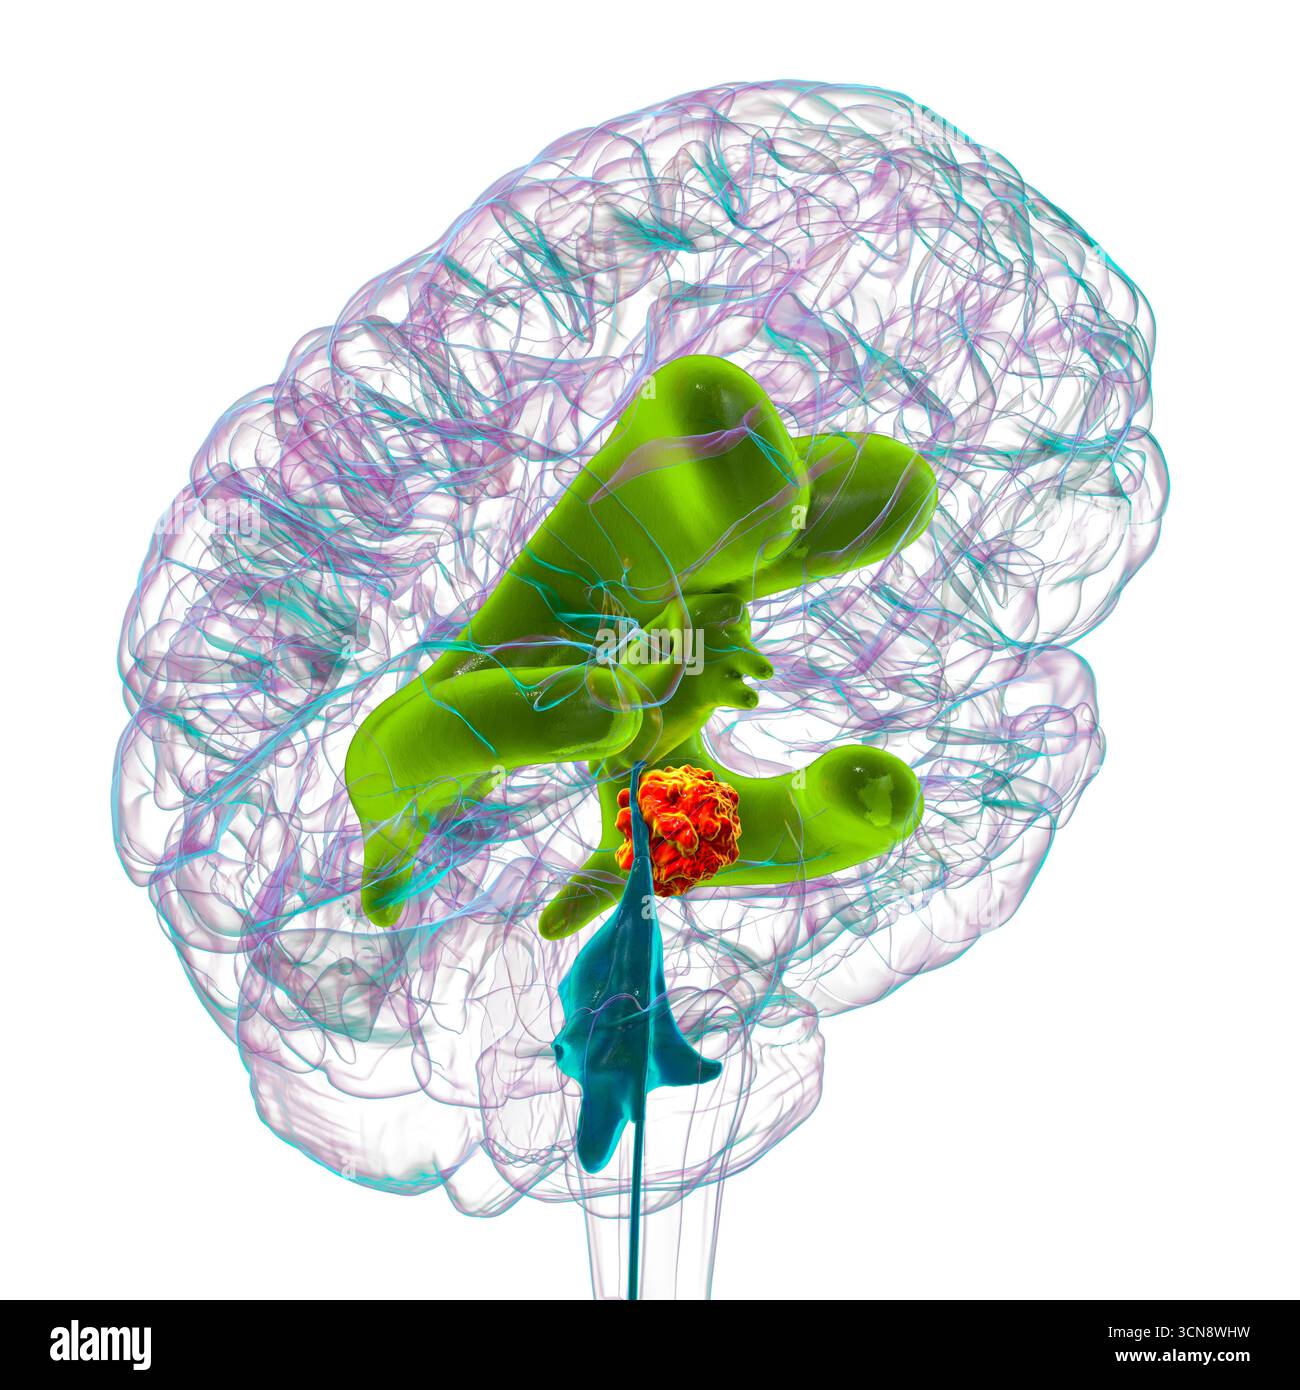

RF3CN8WHW–Darstellung der vergrößerten lateralen und dritten Ventrikel des Gehirns (Hydrozephalus), hervorgerufen durch einen Hirntumor, der den Aquädukt des Gehirns komprimiert.

RF3CN8WHP–Illustration des vergrößerten lateralen und dritten Ventrikels des Gehirns (Hydrozephalus), hervorgerufen durch einen Hirntumor, der den Aquädukt des Gehirns komprimiert.

RF3CPM9D2–Darstellung der vergrößerten lateralen und dritten Ventrikel des Gehirns (Hydrozephalus), hervorgerufen durch einen Hirntumor, der den Aquädukt des Gehirns komprimiert.

RF3CPM9D7–Darstellung der vergrößerten lateralen und dritten Ventrikel des Gehirns (Hydrozephalus), hervorgerufen durch einen Hirntumor, der den Aquädukt des Gehirns komprimiert.

RF3CPM9DA–Darstellung der vergrößerten lateralen und dritten Ventrikel des Gehirns (Hydrozephalus), hervorgerufen durch einen Hirntumor, der den Aquädukt des Gehirns komprimiert.

RF3CPM9D6–Darstellung der vergrößerten lateralen und dritten Ventrikel des Gehirns (Hydrozephalus), hervorgerufen durch einen Hirntumor, der den Aquädukt des Gehirns komprimiert.